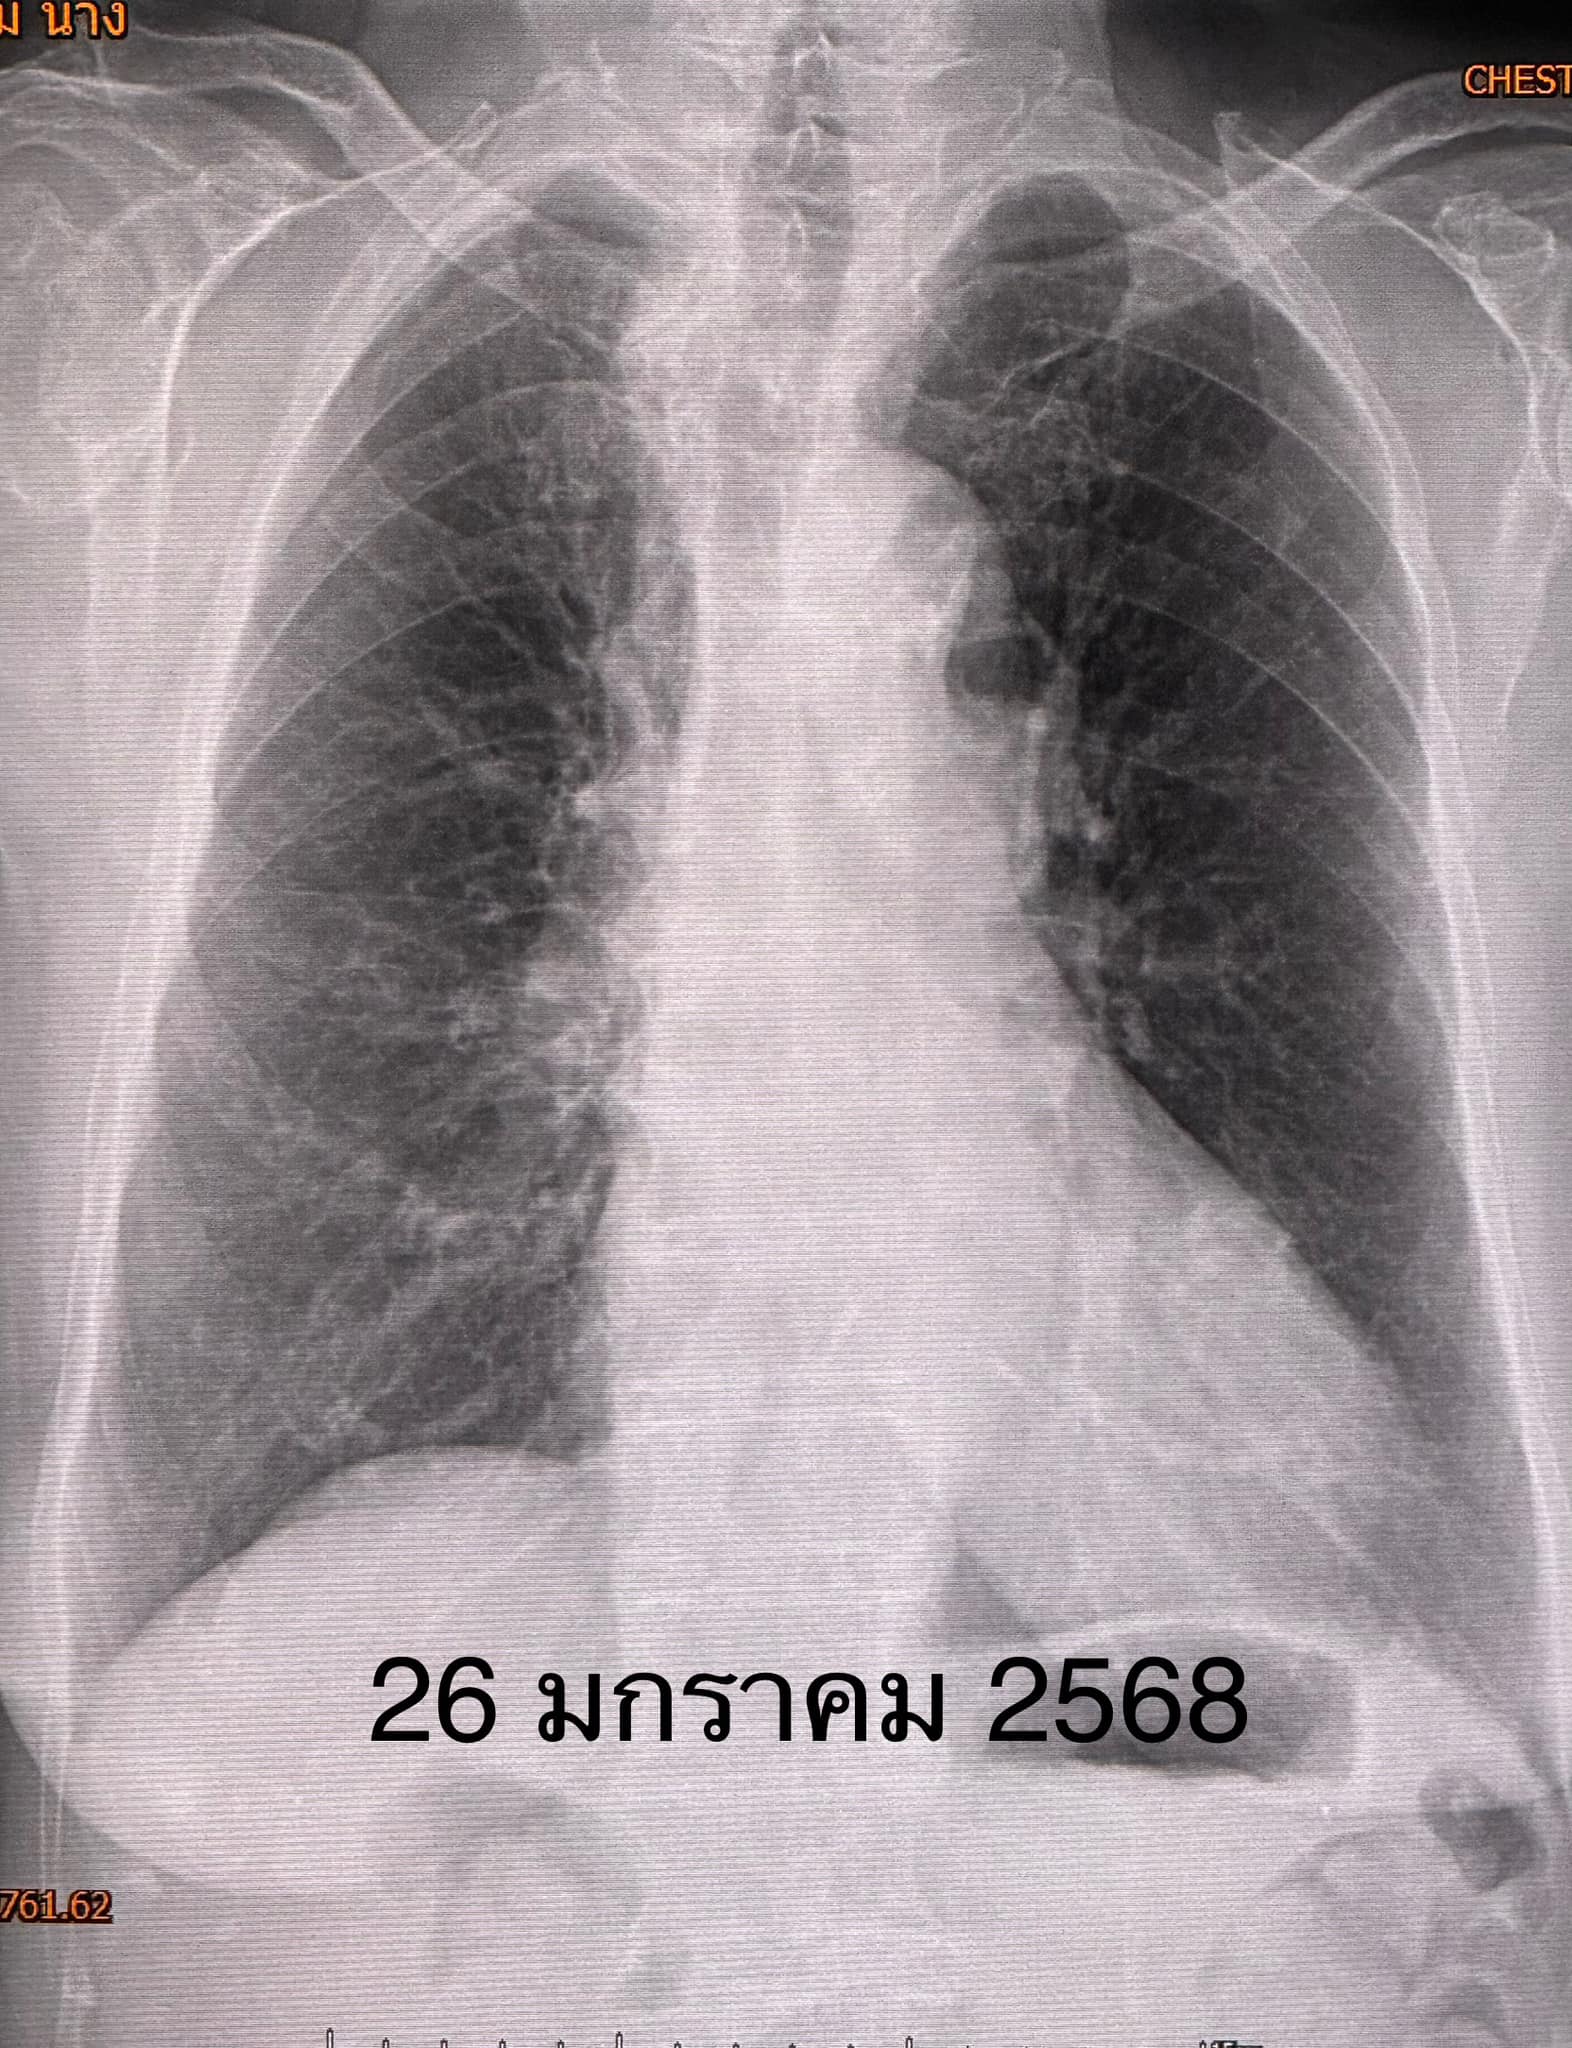

“วินิจฉัย: ติดเชื้อแบคทีเรียลีจิโอเนลลา นิวโมฟิลา Legionella pneumophila ทำให้ปอดอักเสบ ให้ยา azithromycin และ levofloxacin คนไข้ดีขึ้น ไม่ไอ ไม่เหนื่อย ระดับออกซิเจนปกติ ไม่ต้องใช้ออกซิเจน วันที่ 26 มกราคมเอกซเรย์ปอดกลับมาเป็นปกติ (ดูรูป)”